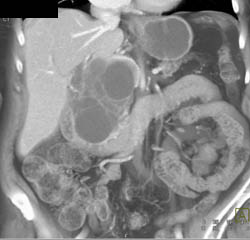

Liver Abscess and Infarction